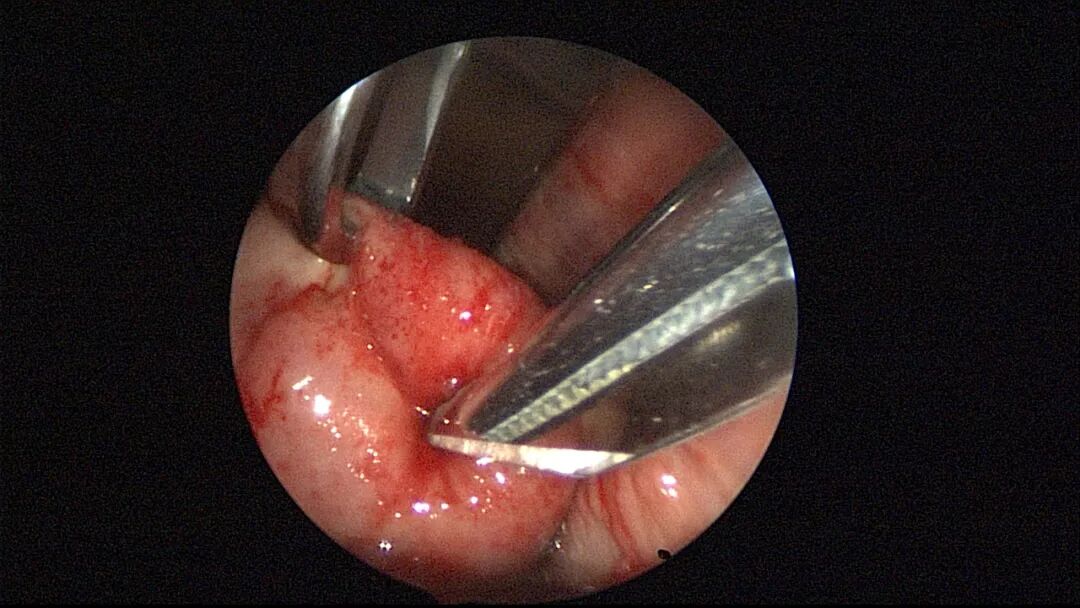

外院取环失败,宫颈暴露困难,缝合牵拉宫颈,尖刀片切开宫颈前唇,扩宫棒顺利扩开宫颈

外院取环失败,宫颈外口封闭,尖刀片切开宫颈